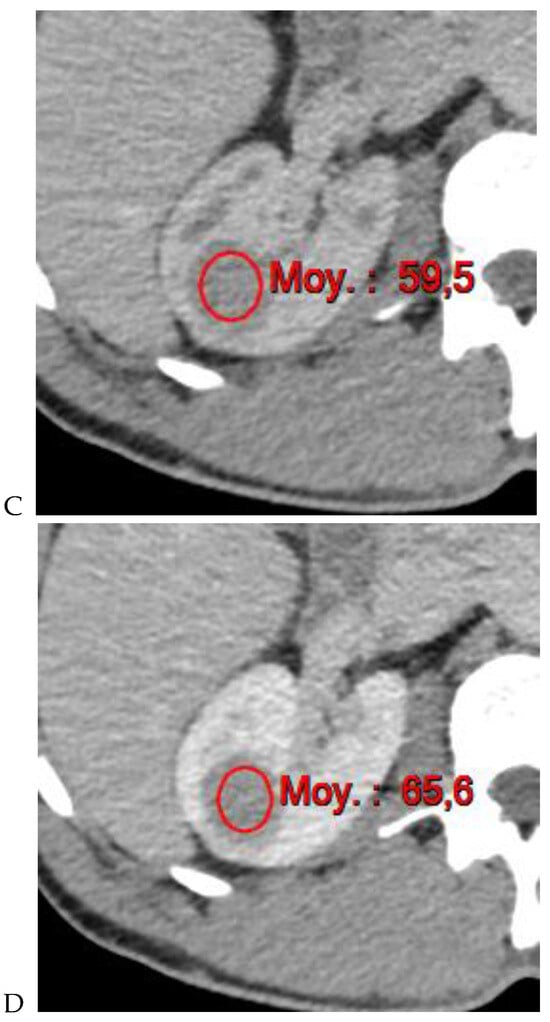

Figure 4.

Multiphasic CT enhancement of a papillary renal cell carcinoma in the middle part of the right kidney of a 63-year-old woman. (A) Mean unenhanced attenuation was 35 HU. (B) Mean corticomedullary phase attenuation was 45 HU. (C) Mean nephrographic phase attenuation was 59 HU. (D) Mean excretory phase attenuation was 65 HU.

Along with unenhanced images, enhancement on multiphasic CT provides a simple, noninvasive means of suggesting the histologic type of a renal mass. It is defined by an increase of 20 HU or more between precontrast and contrast-enhanced images [11]. In daily practice, an enhancement of <10 HU is considered to be characteristic of a cyst, 10–19 HU of an indeterminate mass, and >20 HU suggestive of a renal tumor. Young et al. [9] showed that the mean enhancement of clear cell RCC (Figure 1) was significantly greater than that of oncocytoma (Figure 2) and chromophobe RCC (Figure 3) in the cortico-medullary and excretory phases, and significantly greater than that of papillary RCC (Figure 4) in the cortico-medullary, nephrographic, and excretory phases. In their series, the mean attenuation values during the corticomedullary phase were 125.0 HU for RCCs, 106.0 HU for oncocytomas, 53.6 HU for papillary RCCs, and 73.8 HU for chromophobe RCCs. However, this quantitative information does not necessarily translate into clinically meaningful measures in daily practice due to the variability and overlap in HU measurements. In a recently published study of 87 patients with 93 pathologically proven papillary RCCs [31], most papillary RCCs presented as a hypovascular, circumscribed, solid renal mass; a few (17%) papillary RCCs presented as the newly defined Bosniak class IIF subtype.